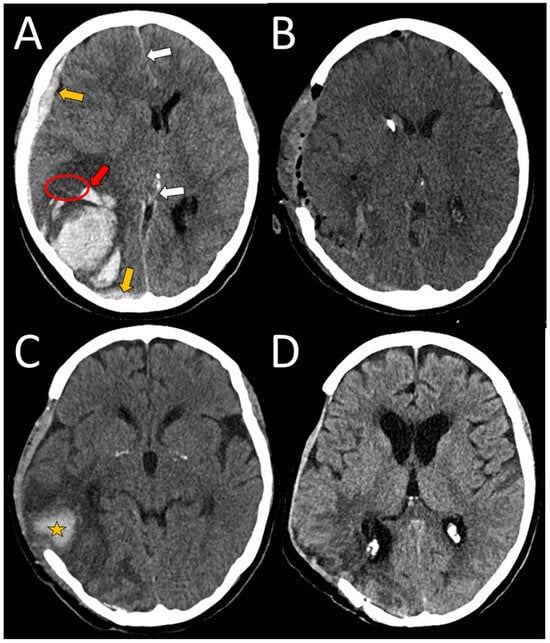

A 75-year-old right-handed female presented to the neurological emergency department (NED), University Medical Centre (UMC) Ljubljana, in February 2025 with confusion, speech impairment, and headache. Her medical history included hypercholesterolemia, arterial hypertension (AH), and a mood disorder with a premorbid modified Rankin score (mRS) of zero. Neurological examination revealed lip smacking, sensorimotor dysphasia, motor restlessness on the right side, and neglect for tactile stimuli on the right (National Stroke Scale score (NIHSS) 4, mRS 2). Her arterial blood pressure was 175/79 mmHg, and electrocardiogram (ECG) showed sinus rhythm. Laboratory tests, including coagulation studies and tumor markers, were normal, and chest X-ray findings were unremarkable. A head CT scan revealed a heterogeneous lobar ICH in the left parietotemporal lobe, accompanied by an SDH encircling the left cerebral hemisphere, as well as transtentorial herniation (Figure 1A,B). CT angiography was unremarkable, and cerebral venous sinuses and major veins were patent. She was initially treated with levetiracetam due to motor automatisms, which improved after administration but dysphasia remained. Her clinical condition deteriorated later that day, with the development of nausea, vomiting, right-sided spastic hemiparesis, and eye deviation to the left. Follow-up non-contrast head CT revealed hematoma expansion (4.5 × 7 × 4 cm) and increased edema. Urgent ICH hematoma evacuation was performed (Figure 1C,D), and a cortical biopsy was obtained during the same operating session for histopathological analysis, which identified Aβ deposits in the blood vessel walls, confirming CAA (Figure 2). The patient was transferred to the intensive care unit (ICU). Three days after admission, analgosedation was discontinued, revealing sensory-motor dysphasia as the only persistent neurological impairment. On the fifth day of admission, an electroencephalogram was performed, revealing no abnormalities suggestive of epilepsy; however, asymmetry was noted, with a predominance of slow-wave patterns and lower amplitudes in the left hemisphere. She was transferred to a regular ward. Follow-up CT imaging almost one month after admission showed ICH resorption. She became increasingly difficult to manage, initially exhibiting apathic behavior, which later progressed to episodes of excessive agitation, disinhibition, and aggressive outbursts, and eventually followed by psychotic symptoms, necessitating treatment with antidepressants, a mood stabilizer, and an antipsychotic medication.

Figure 1. An unenhanced initial CT scan of a spontaneous heterogeneous ICH in the left temporal area (coronal views (A,B)), measuring 3.7 × 7 × 3 cm. Concomitant subdural hematoma and SAH can be seen (orange arrow), as can finger-like extensions of the bleeding in the brain parenchyma (red arrows). Axial and coronal views after the surgical evacuation ((C,D), respectively). The ellipse denotes the area of surgical biopsy.